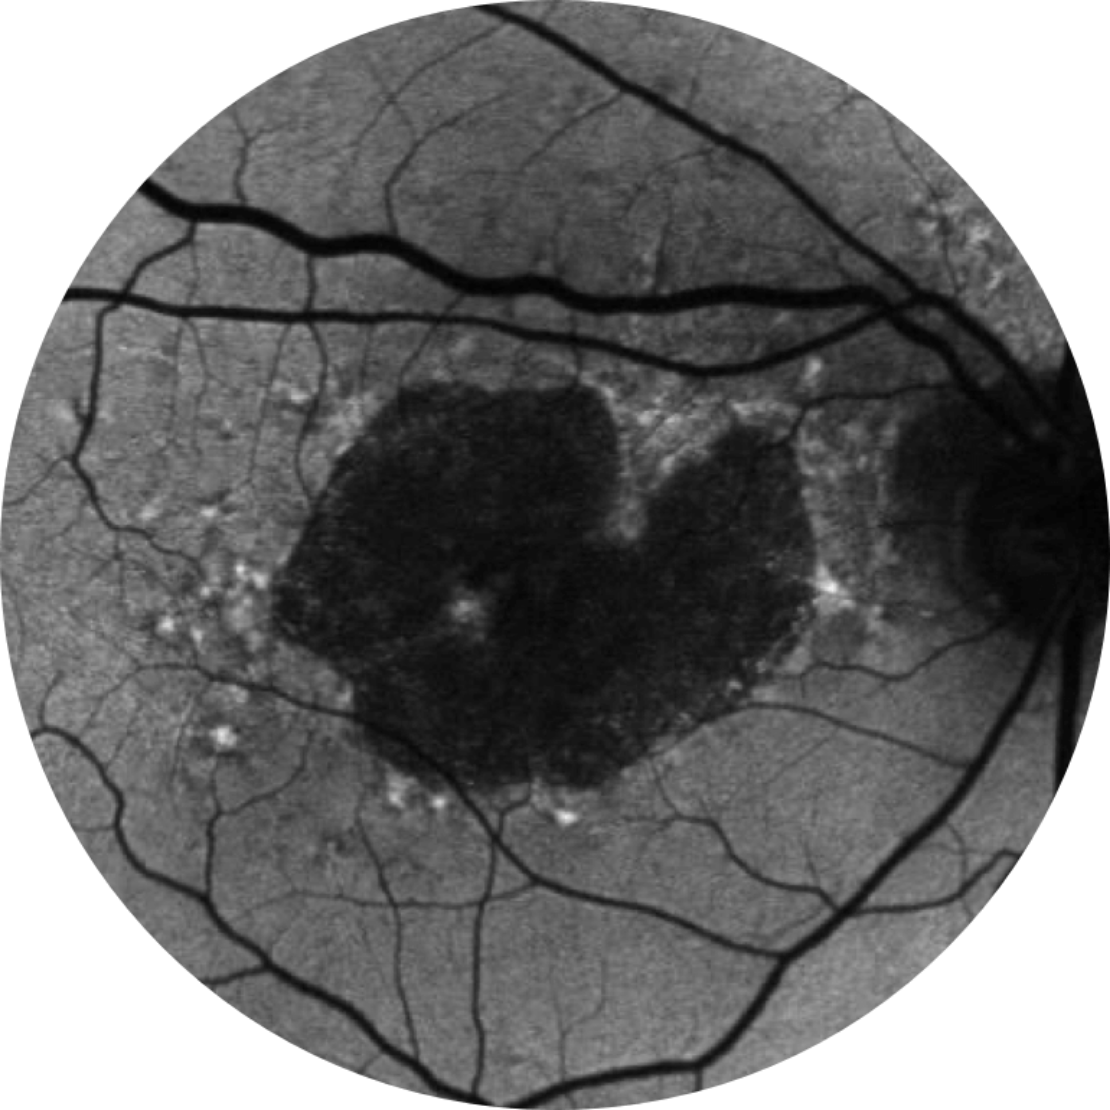

Normale Fundusautofluoreszenz einer Netzhaut

Die Fundus-Autofluoreszenz ist derzeit eine standardmäßige Bildgebungstechnologie zur Visualisierung des retinalen Pigmentepithels (RPE) bei Geographischer Atrophie.20